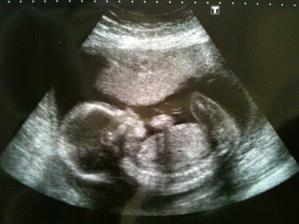

@evelin116 dakujem, to bolo v 20 tyzdni. Pekna fotocka, ale nozicky malo prekrizene, takze nevieme co budeme mat 🙂